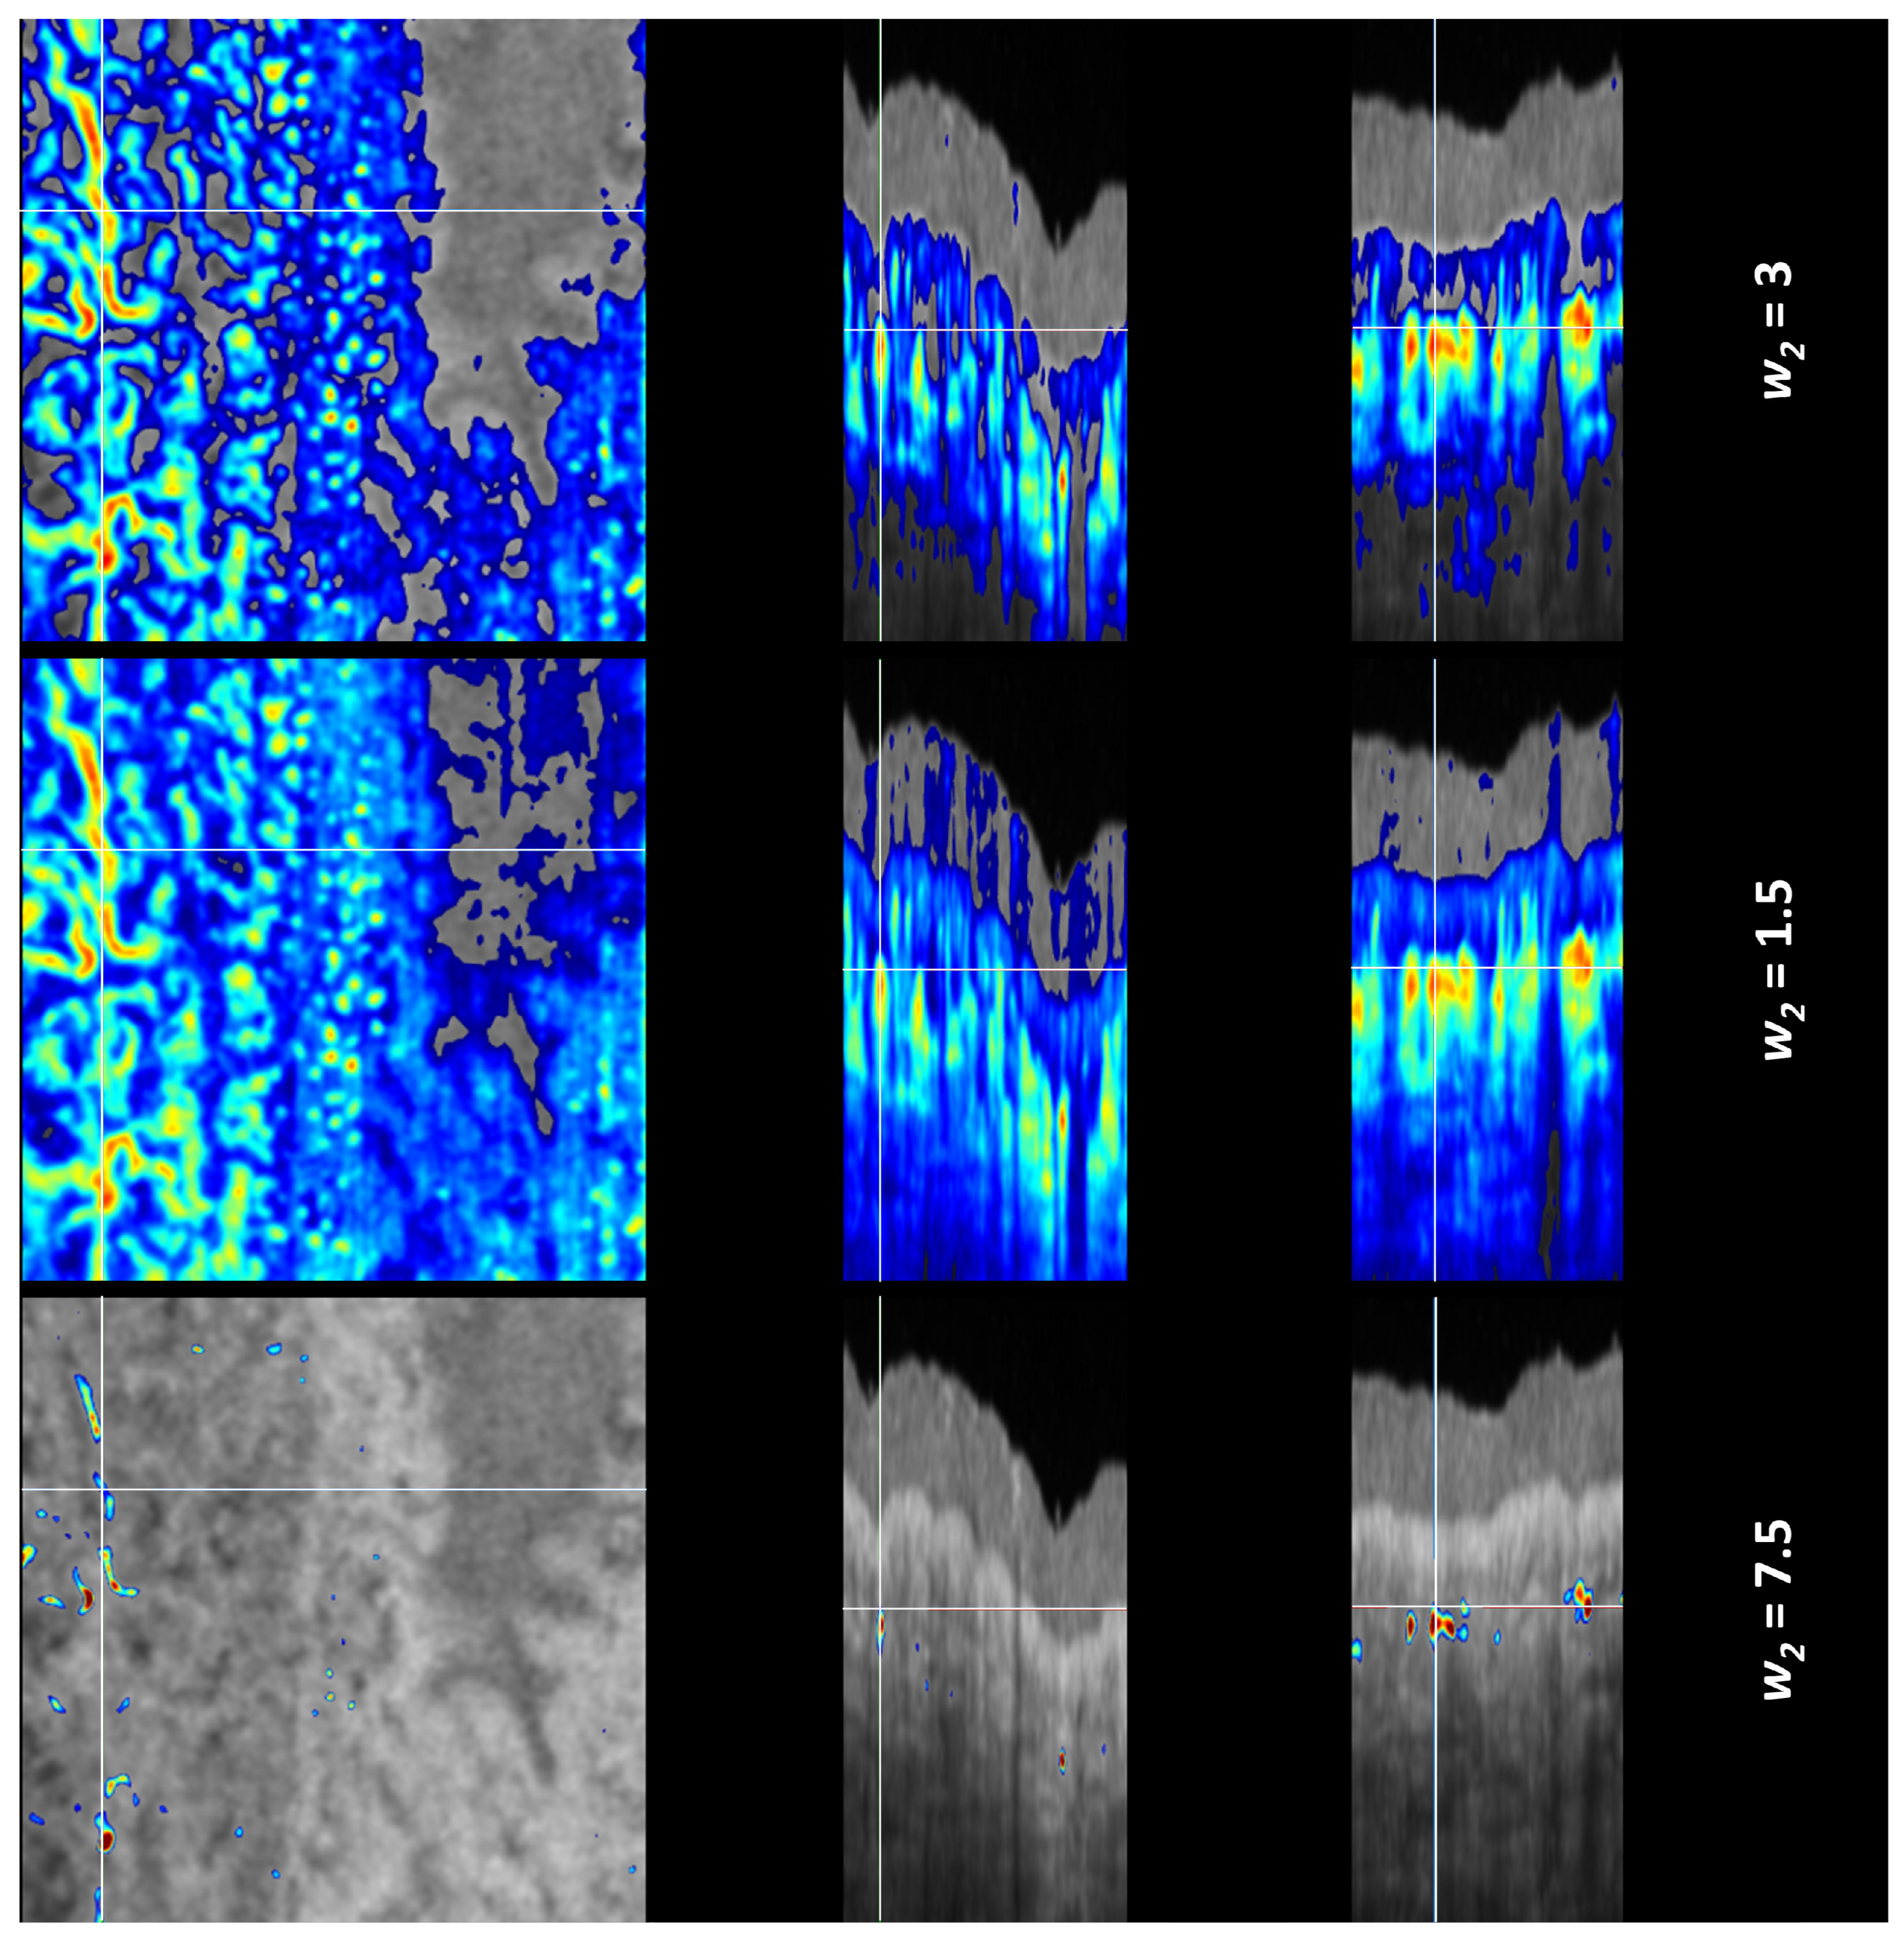

In essence, the Mean-Subtraction algorithm subtracts a baseline value for each OCTA A-scan. The subtracted baseline is different for each OCTA A-scan, so the method is similar to the window setting. In some parts of the corrected OCTA image, the signal is missing because the original OCTA was lower than the subtracted value. When the weight is below the optimal value, the tail artifact is less effectively corrected—seen when comparing the first and the second row. When these images are compared (the first row with the w2 = 3 that is considered as an optimal and the second row with the w2 = 1.5), the differences appear to be small. Therefore, we consider that the range of optimal weight values is broad and manual adjustment is sufficient. If the weight is too high (third row in Figure 6), almost the whole image disappears, which is easy to notice. Due to this substantial difference, the correction with intermediate correction weight values is presented in Figure 7. As we see, the tail artifact is disappearing when the correction weight is increasing, and also the amount of vasculature visible on en face image is reduced.

Figure 6. Corrected OCTA images with the Mean-Subtraction algorithm for three correction weights. On the left is the en face view, in the middle is the B-scan cross-sectional view, and on the right is the C-scan cross-sectional view. The first row shows the corrected OCTA with the weight that we consider optimal, the second row shows the correction with two-times lower weight, and the third row shows the correction with a 2.5-times higher weight. (Note that the color scale is different for each row).